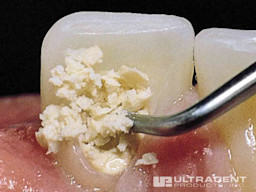

Step 3

Wipe excess easily with wet gauze or cotton swab before setting.

Step 4

Finished.

Step 5

Remove easily.